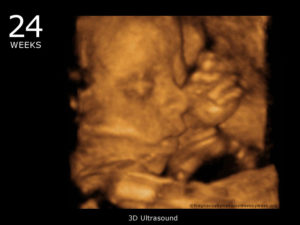

- четвёртый раз, уже можно сделать 3D УЗИ — в 22-24 недели

4-мерное ультразвуковое исследование можно проводить в любые сроки беременности, начиная с 8 недель. В этот период длина эмбриона составляет 15-16 мм. Но оптимальный срок — это 20-25 недель, когда плод уже достигает значительного развития.

4D следует начинать проходить примерно с 20-й недели беременности. Этот срок определен не случайно, картинка, полученная на 20-й акушерской неделе, получится более реалистичной.